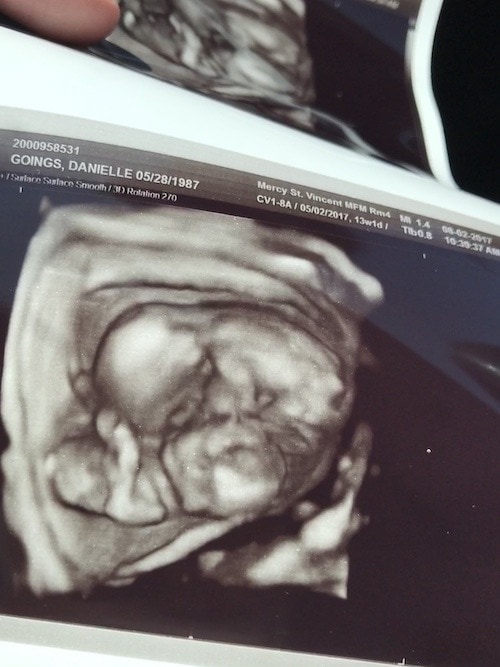

- Ultrasound Photos at 13 Weeks Pregnant With Twin

Ultrasound Photos at 13 Weeks Pregnant With Twin